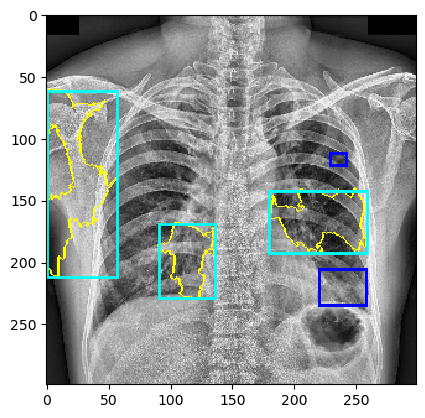

The behavior of MindfulLIME compared to LIME is demonstrated in Figures 4 and 5. Figure 4 showcases random sample 1 with a detected Pleural Effusion condition (annotations highlighted in green), while Figure 5 features random sample 2 with a detected Lung Opacity condition (annotations highlighted in blue). Each figure illustrates the disparities between the ground-truth annotations (darker-colored rectangles) and the generated explanations (lighter-colored rectangles surrounding the yellow border of the selected superpixels). We would like to emphasize that our trained classifier model generalizes well and is not simply memorizing the training data, as evidenced by its performance on a separate evaluation dataset.

The left columns depict the results for the top 1 feature, while the right columns display the results for the top 4 features. The first row presents the output of MindfulLIME, while the second and third rows represent the results of LIME using 1000 and 4000 samples, respectively. When comparing the results of LIME and MindfulLIME for two visual random samples, it becomes evident that MindfulLIME excels in multiple aspects. Firstly, MindfulLIME consistently identifies the top 1 feature with the highest similarity with the actual bounding box. Additionally, as the number of top features increases, MindfulLIME effectively prioritizes and presents more relevant features at the forefront. These findings highlight the enhanced performance and prioritization capabilities of MindfulLIME compared to LIME.